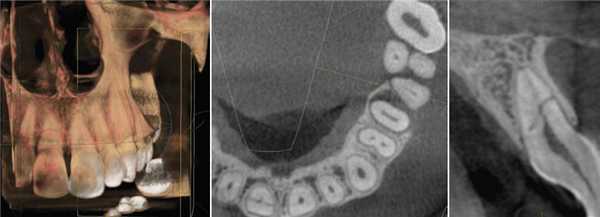

На томограммах и реконструктивных снимках было установлено, что 4.6, 4.7 зубы имеют особенность микроанатомии каналов. Мезиальные корни содержали по 2 канала, которые открывались отдельными апикальными отверстиями. В дистальных корнях обнаружили по 3 канала, которые сливались в одно апикальное отверстие. Причем третий (дистально-язычный) канал 4.7 зуба заканчивался на язычной стенке корня на уровне его середины (рис. 2) .

Рис. 2. КЛКТ. Аксиальные последовательные срезы 4.6, 4.7 зубов.

Качество пломбирования 4.7 зуба, по данным КЛКТ, было неудовлетворительным. В мезиально-щечном и дистальных каналах 4.7 зуба пломбировочный материал прослеживался в виде отдельных фрагментов (рис. 3) . Мезиально-язычный канал обтурирован неплотно, до апикальной стриктуры (рис. 4). Наблюдали признаки апикальной резорбции дистального корня (рис. 5) .